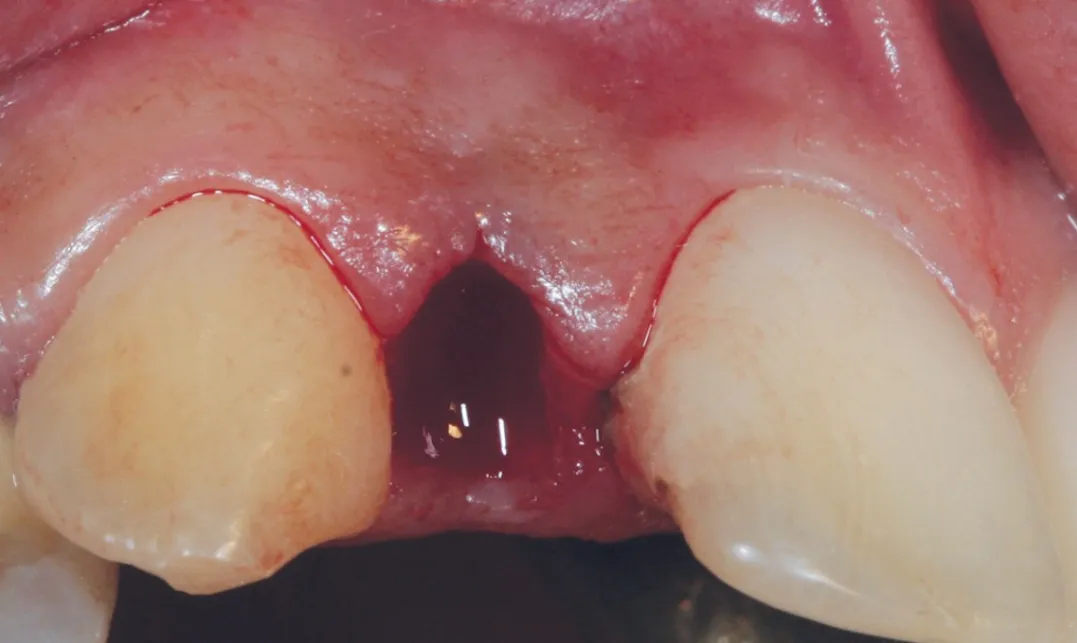

2 号病例 - Patrick EXBRAYAT 医生(图 21 至 35)

22 岁患者,23 异位,行正颌外科种植术后 22 出现严重根吸收。

图 21 :术前临床检查。

图 23 :拔牙后手术区域。